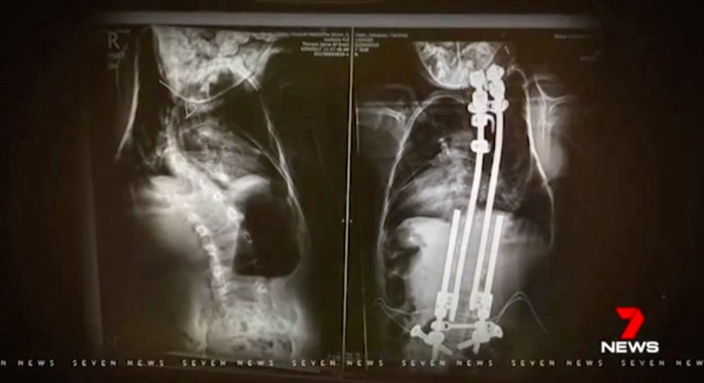

與此同時,如果按照傳統的治療方法,醫生會在患者體內植入一根固定長度的人造脊椎,就像一根木棍一樣扶直嚴重彎曲的脊椎。但由於Dempsey尚年幼,身體還會繼續發育,因此這根人造脊椎只能暫時性讓他的背部直立起來,而且未來還可能會讓長高的他動彈不得,甚至是造成致命的危險。

Deroussen醫生解釋,這根「骨頭」看起來就像足球場上的球門柱,長桿位於中間,短桿則位於外側,利用伸縮原理來讓它「隨著Dempsey的發育而不斷伸長,自動適應他的身體結構」。在對Dempsey進行了全身3D掃描,且在假人身上反復模擬演練過後,這宗澳洲醫學界內史無前例的手術開始了。

最終,在經過3小時的煎熬後,Deroussen醫生宣布手術成功,Dempsey的母親不禁哭著感歎:「我不敢相信這種奇跡會發生在我兒子身上。」手術後3個月,脊椎原本嚴重畸變的Dempsey一躍長高了12厘米,現在的他不但能夠騎馬、打籃球,還能回到了他熱愛的足球場上,和普通孩子一起開心地在綠茵場上享受足球樂了。